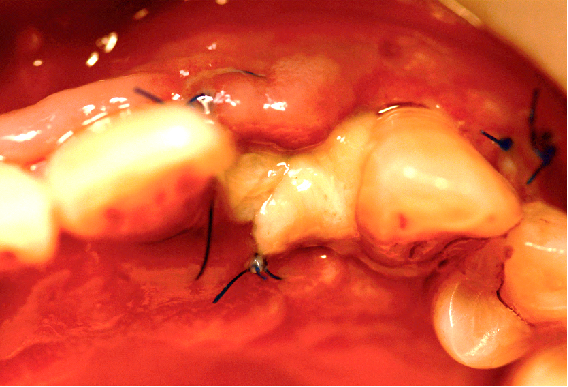

缝合手术切口

瑞拜欧可吸收生物膜具有一定抗菌活性,复合PRF保护,尝试拔牙创开放愈合,保证了龈乳头原位缝合、避免了膜龈联合位置异位,有利于日后的美学效果,术后常规口腔护理、漱口、服用抗生素5天。

术后5天 拆线

牙龈稍显红肿,清洁、无感染迹象,伤口内可见纤维蛋白覆盖。

拆除缝线后牙龈情况。

切口区域上抑菌凝胶,嘱患者常规漱口、口腔卫生维护,勿用力“鼓腮”式漱口。